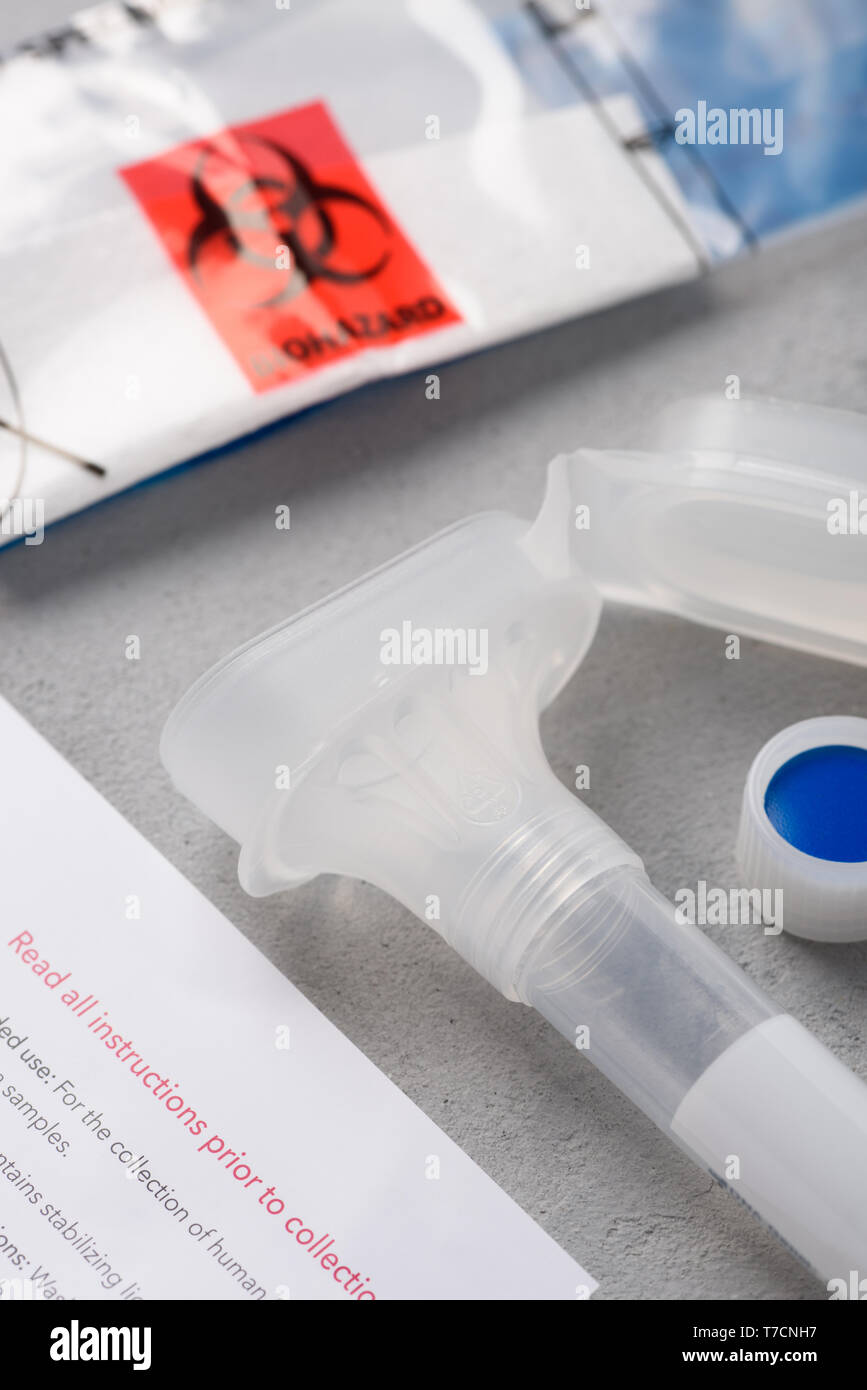

DNA diagnosis saliva consumer genetic ancestry collection kit Stock Photohttps://www.alamy.com/image-license-details/?v=1https://www.alamy.com/dna-diagnosis-saliva-consumer-genetic-ancestry-collection-kit-image245528115.html

DNA diagnosis saliva consumer genetic ancestry collection kit Stock Photohttps://www.alamy.com/image-license-details/?v=1https://www.alamy.com/dna-diagnosis-saliva-consumer-genetic-ancestry-collection-kit-image245528115.htmlRFT7CNH7–DNA diagnosis saliva consumer genetic ancestry collection kit